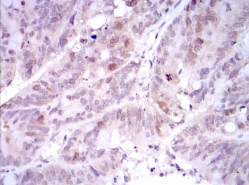

| AC3208 | PLK1 Mouse Monoclonal antibody[3C110] | 100ug | $367 | 10days |

| AC3208 | PLK1 Mouse Monoclonal antibody[3C110] | 200ug | $660.6 | 10days |